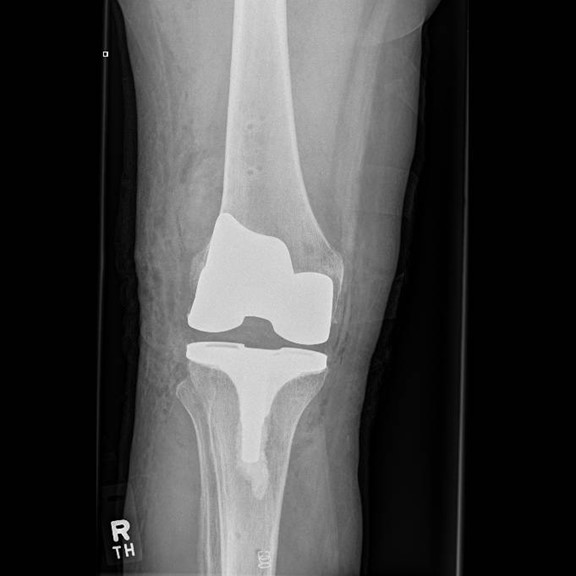

Unlike other robotic systems with the CORI robotic assisted total knee replacement there is no need for further imaging scans such as a CT and therefore radiation exposure is reduced. During a CORI robotic assisted total knee replacement the knee is mapped during surgery using a probe. Tracers can monitor the movement and stability of the knee and an accurate 3D model of the knee is created by the robot. Using this information, the robot can display the optimal sizing and positioning for the implants to enable a balanced, full range of motion. With this level of accuracy, the longevity, function and feel of the knee implant can be improved.

Through a midline incision the surfaces of the bone can be replaced. The femoral component is a smooth metal component of varying sizes, which fits over the end of the femur. The tibial component consists of a metal base plate that sits on top of the tibia and a polyethelene (plastic) insert that fixes onto the tibial component. The patella surface may be replaced if it is worn. The implants are positioned and fixed to the bone using bone cement.